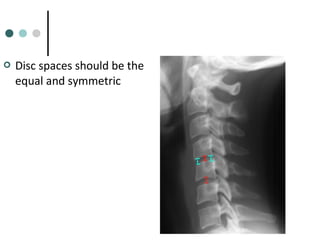

 Disc spaces should be the

equal and symmetric

 Disc spacesshould be the equal and symmetric